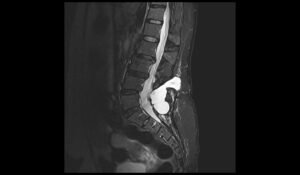

CSF leak MRI | Radiology article on CSF leak